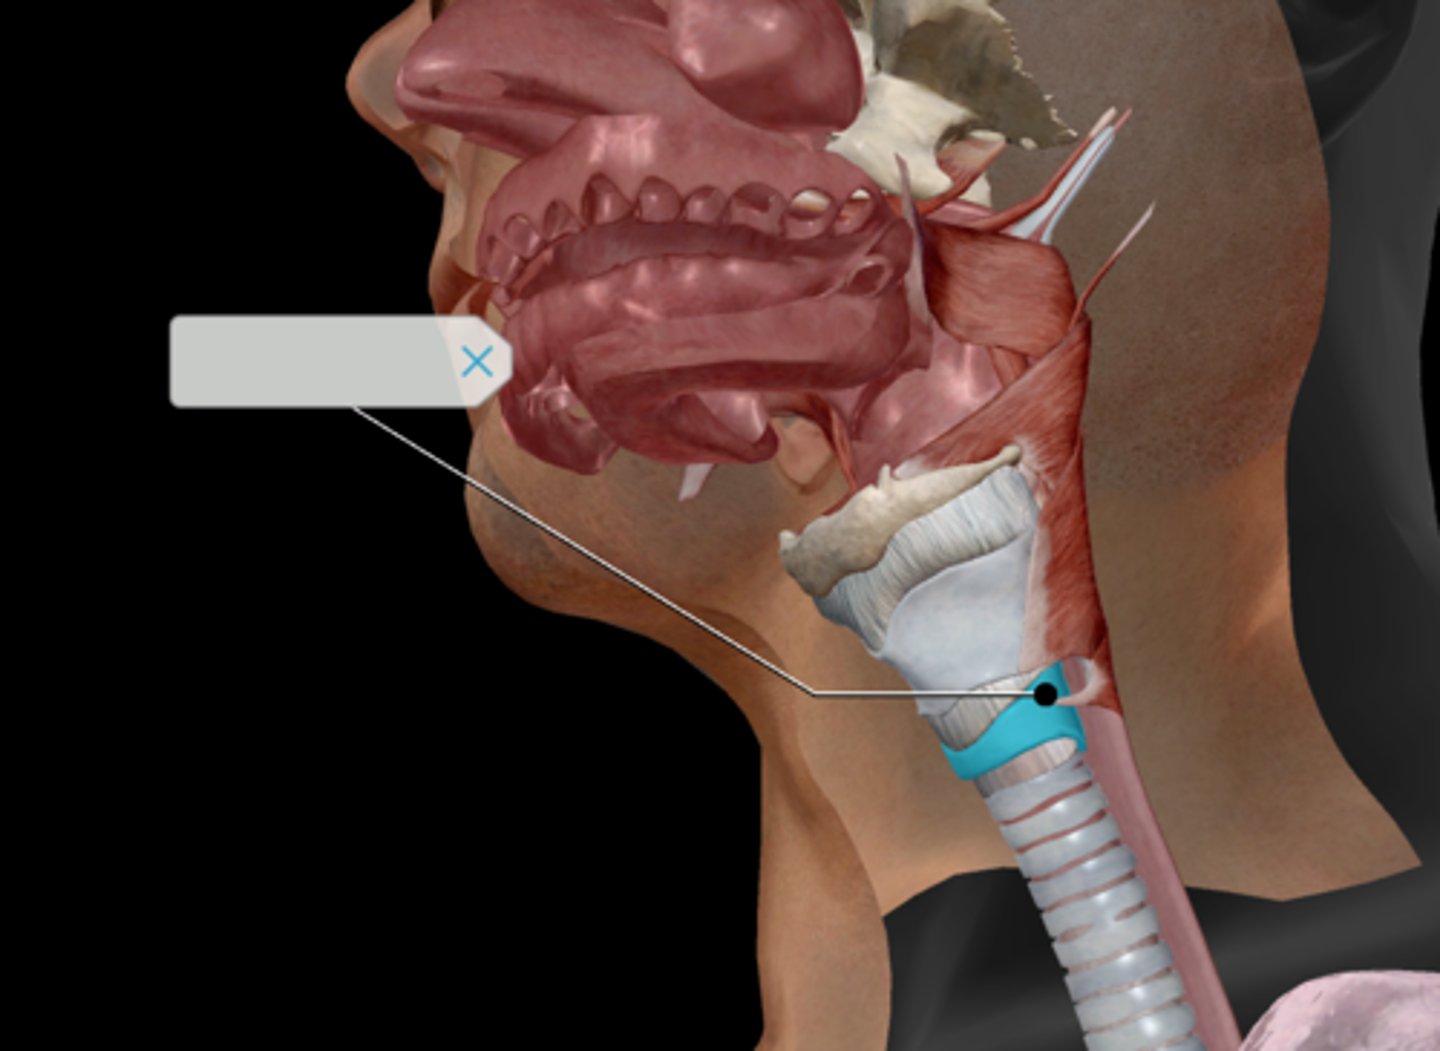

Nasopharynx

Oropharynx

Laryngopharynx

Larynx

Epiglottis

Thyroid cartilage

Cricoid cartilage

Trachea

Tracheal cartilaginous rings

Vagus nerve (CN X)

Medulla oblongata

Glossopharyngeal nerve (CN IX)

Tongue

Hard palate

Soft palate

Palatine tonsil

Uvula